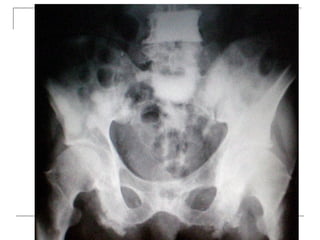

Plain radiograph

   AP

-loss of lumbar lordosis

-reduced disc space

-osteophytes

-deformity

-fracture (increase interpedicular distance)

-osteoporosis

-pedicle disruption

   Lateral

-fracture/wedging

-kyphosis

-spondylolisthesis

   Oblique

-spondylolysis (SCOTTIE DOG)

Plain x-rays

Plain radiograph  AP -loss of lumbar lordosis -reduced disc space -osteophytes -deformity -fracture (increase interpedicular distance) -osteoporosis -pedicle disruption

Lateral -fracture/wedging -kyphosis -spondylolisthesis  Oblique -spondylolysis (SCOTTIE DOG)